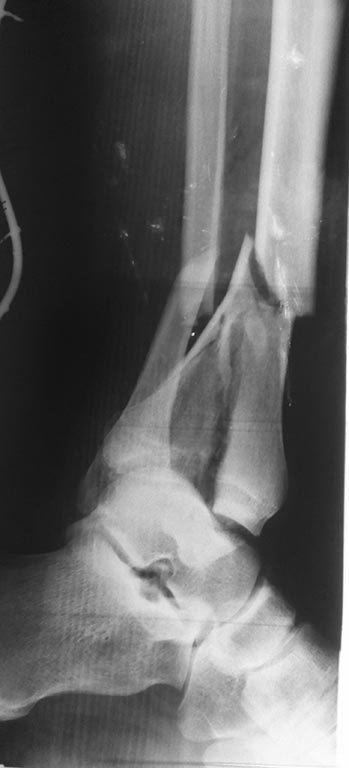

Снимки при поступлении, спустя 2,5 месяца. Рентген снимки после снятия

аппарата в архиве пришлю позже. Осылаю КТ от апреля.